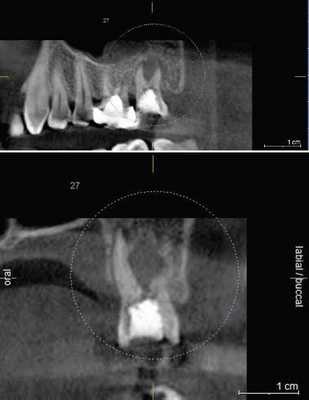

Часто резорбцию выявляют случайно при рентгенологическом исследовании по другому поводу [23] . На рентгенограмме внутренняя и внешняя резорбция будут выглядеть по-разному.

Рентгенологические признаки наружной и внутренней резорбции корня зуба

Воспалительная и заместительная резорбция рентгенологически очень похожи. Но при заместительной резорбции из-за образования кости на снимке не видно просветления в области периодонтальной щели.

Рентгеновское обследование зубов (дентальные рентгенограммы) — самым простой, быстрый и доступный метод диагностики. Но в сложных случаях, когда не удаётся поставить диагноз, лучше использовать компьютерную томографию (КТ). Этот метод более информативный [22] [23] [26] .